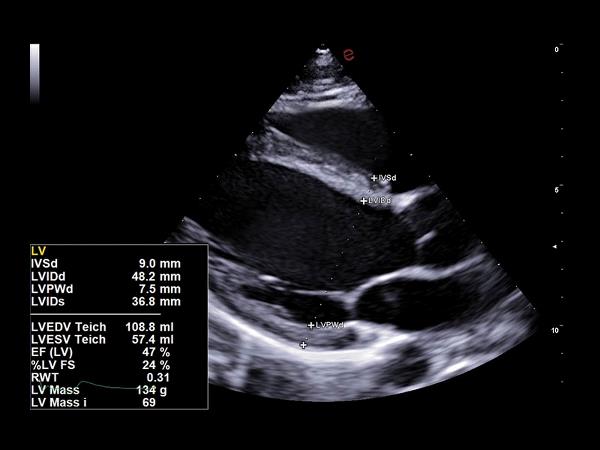

Med sine avancerede funktioner og høje billedkvalitet er MyLab™A70 ideel til et bredt spektrum af anvendelsesområder, fra akutte traumer til komplekse vurderinger. Den intuitive brugerflade gør betjeningen enkel, og de AI-drevne værktøjer hjælper med scanningsarbejdet og lader dig fokusere på patienten.

De indbyggede AI-værktøjer hjælper med automatisk billedoptimering og arbejdsflow, fx eScan, Autoscan og eDoppler. Derudover understøtter A70 avancerede målinger som strain-analyse og lever-elastografi.